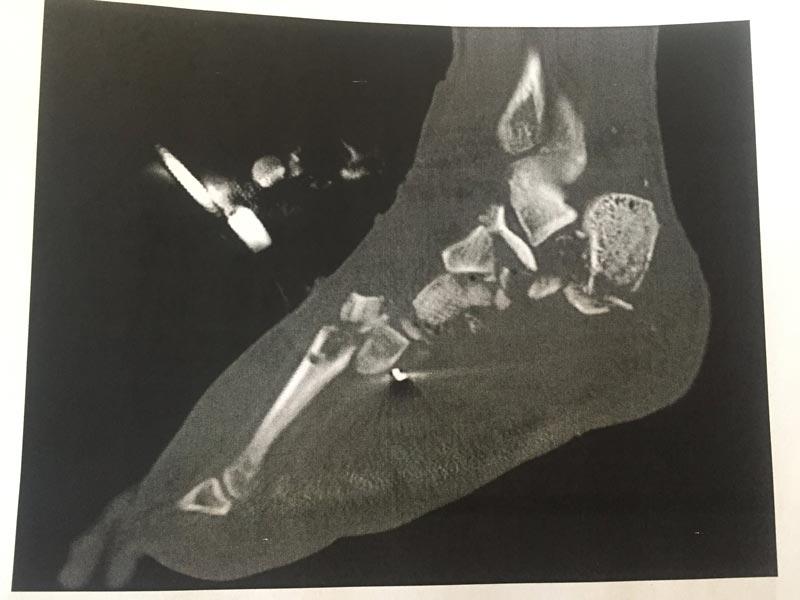

จากการรายงานของเว็บไซต์เดลี่สตาร์ เมื่อวันที่ 13 มิถุนายน 2561 ระบุว่า ตอนนั้นชายหนุ่มคนนี้ประสบอุบัติเหตุรถมอเตอร์ไซค์ล้มคว่ำ ส่งผลให้กระดูกข้อเข้าซ้ายของเขาหักยับเยิน แม้แพทย์จะทำการผ่าตัด เย็บปิดแผล และใช้เหล็กดามไว้แล้ว แต่อาการบาดเจ็บมันรุนแรงเกินกว่าจะรักษาได้ แพทย์จึงต้องตัดเท้าข้างนี้ทิ้ง เพื่อเป็นการรักษาชีวิตเขาเอาไว้ เพราะถ้าปล่อยไว้ก็เสี่ยงต่อการติดเชื้อ อันตรายยิ่งไปกว่าเดิม

ภาพจาก imgur.com